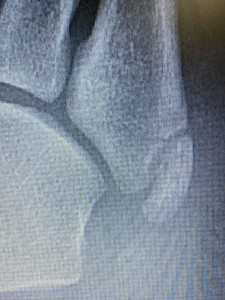

けど、第五中足骨の骨頭を触れると明らかに他の部位とは違う反応が❗️

結果、折れてました😅

この骨折、いわゆる下駄骨折って言って下駄履いて転んだらよくなるやつなんです❗️